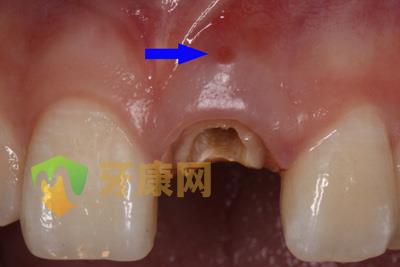

根管側穿修補術,根管側穿是牙髓治療失敗的一個重要原因,常常由不正確的開髓、根擴方法導致,樁核制作時盲目的操作也會造成側穿,側穿部位越及時修補,增加治療成功的可能性越高,下面是根管側穿修補術的一個病例:

患者外院螺紋樁核加樹脂冠,唇側出現瘺管

瘺管